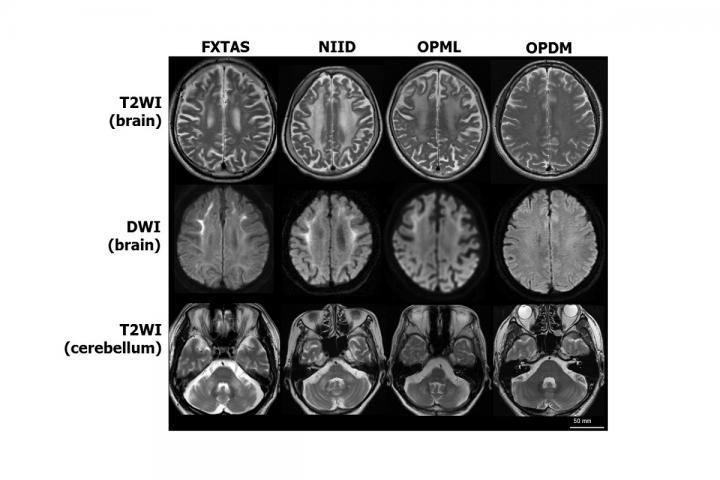

image: Four rare diseases are characterized by similar symptoms of neurodegeneration. Patients with three of the diseases -- fragile X tremor/ataxia syndrome (FXTAS), neuronal intranuclear inclusion disease (NIID) and oculopharyngeal myopathy with leukoencephalopathy (OPML) -- have similar MRI brain scan images. Patients with a fourth disease, oculopharyngodistal myopathy (OPDM), have normal brain scans, but their muscle tissue has a similar appearance to that of patients with OPML. Researchers suspected that the genetic mutations causing the four diseases must also be similar, even if the mutations were in different genes. After exhaustive genetic sequencing and analysis, researchers in Japan discovered that the same mutation -- CGG noncoding expanded tandem repeats -- in different areas of the genome causes all four diseases.

T2WI: T2 weighted image; DWI: Diffusion weighted image.